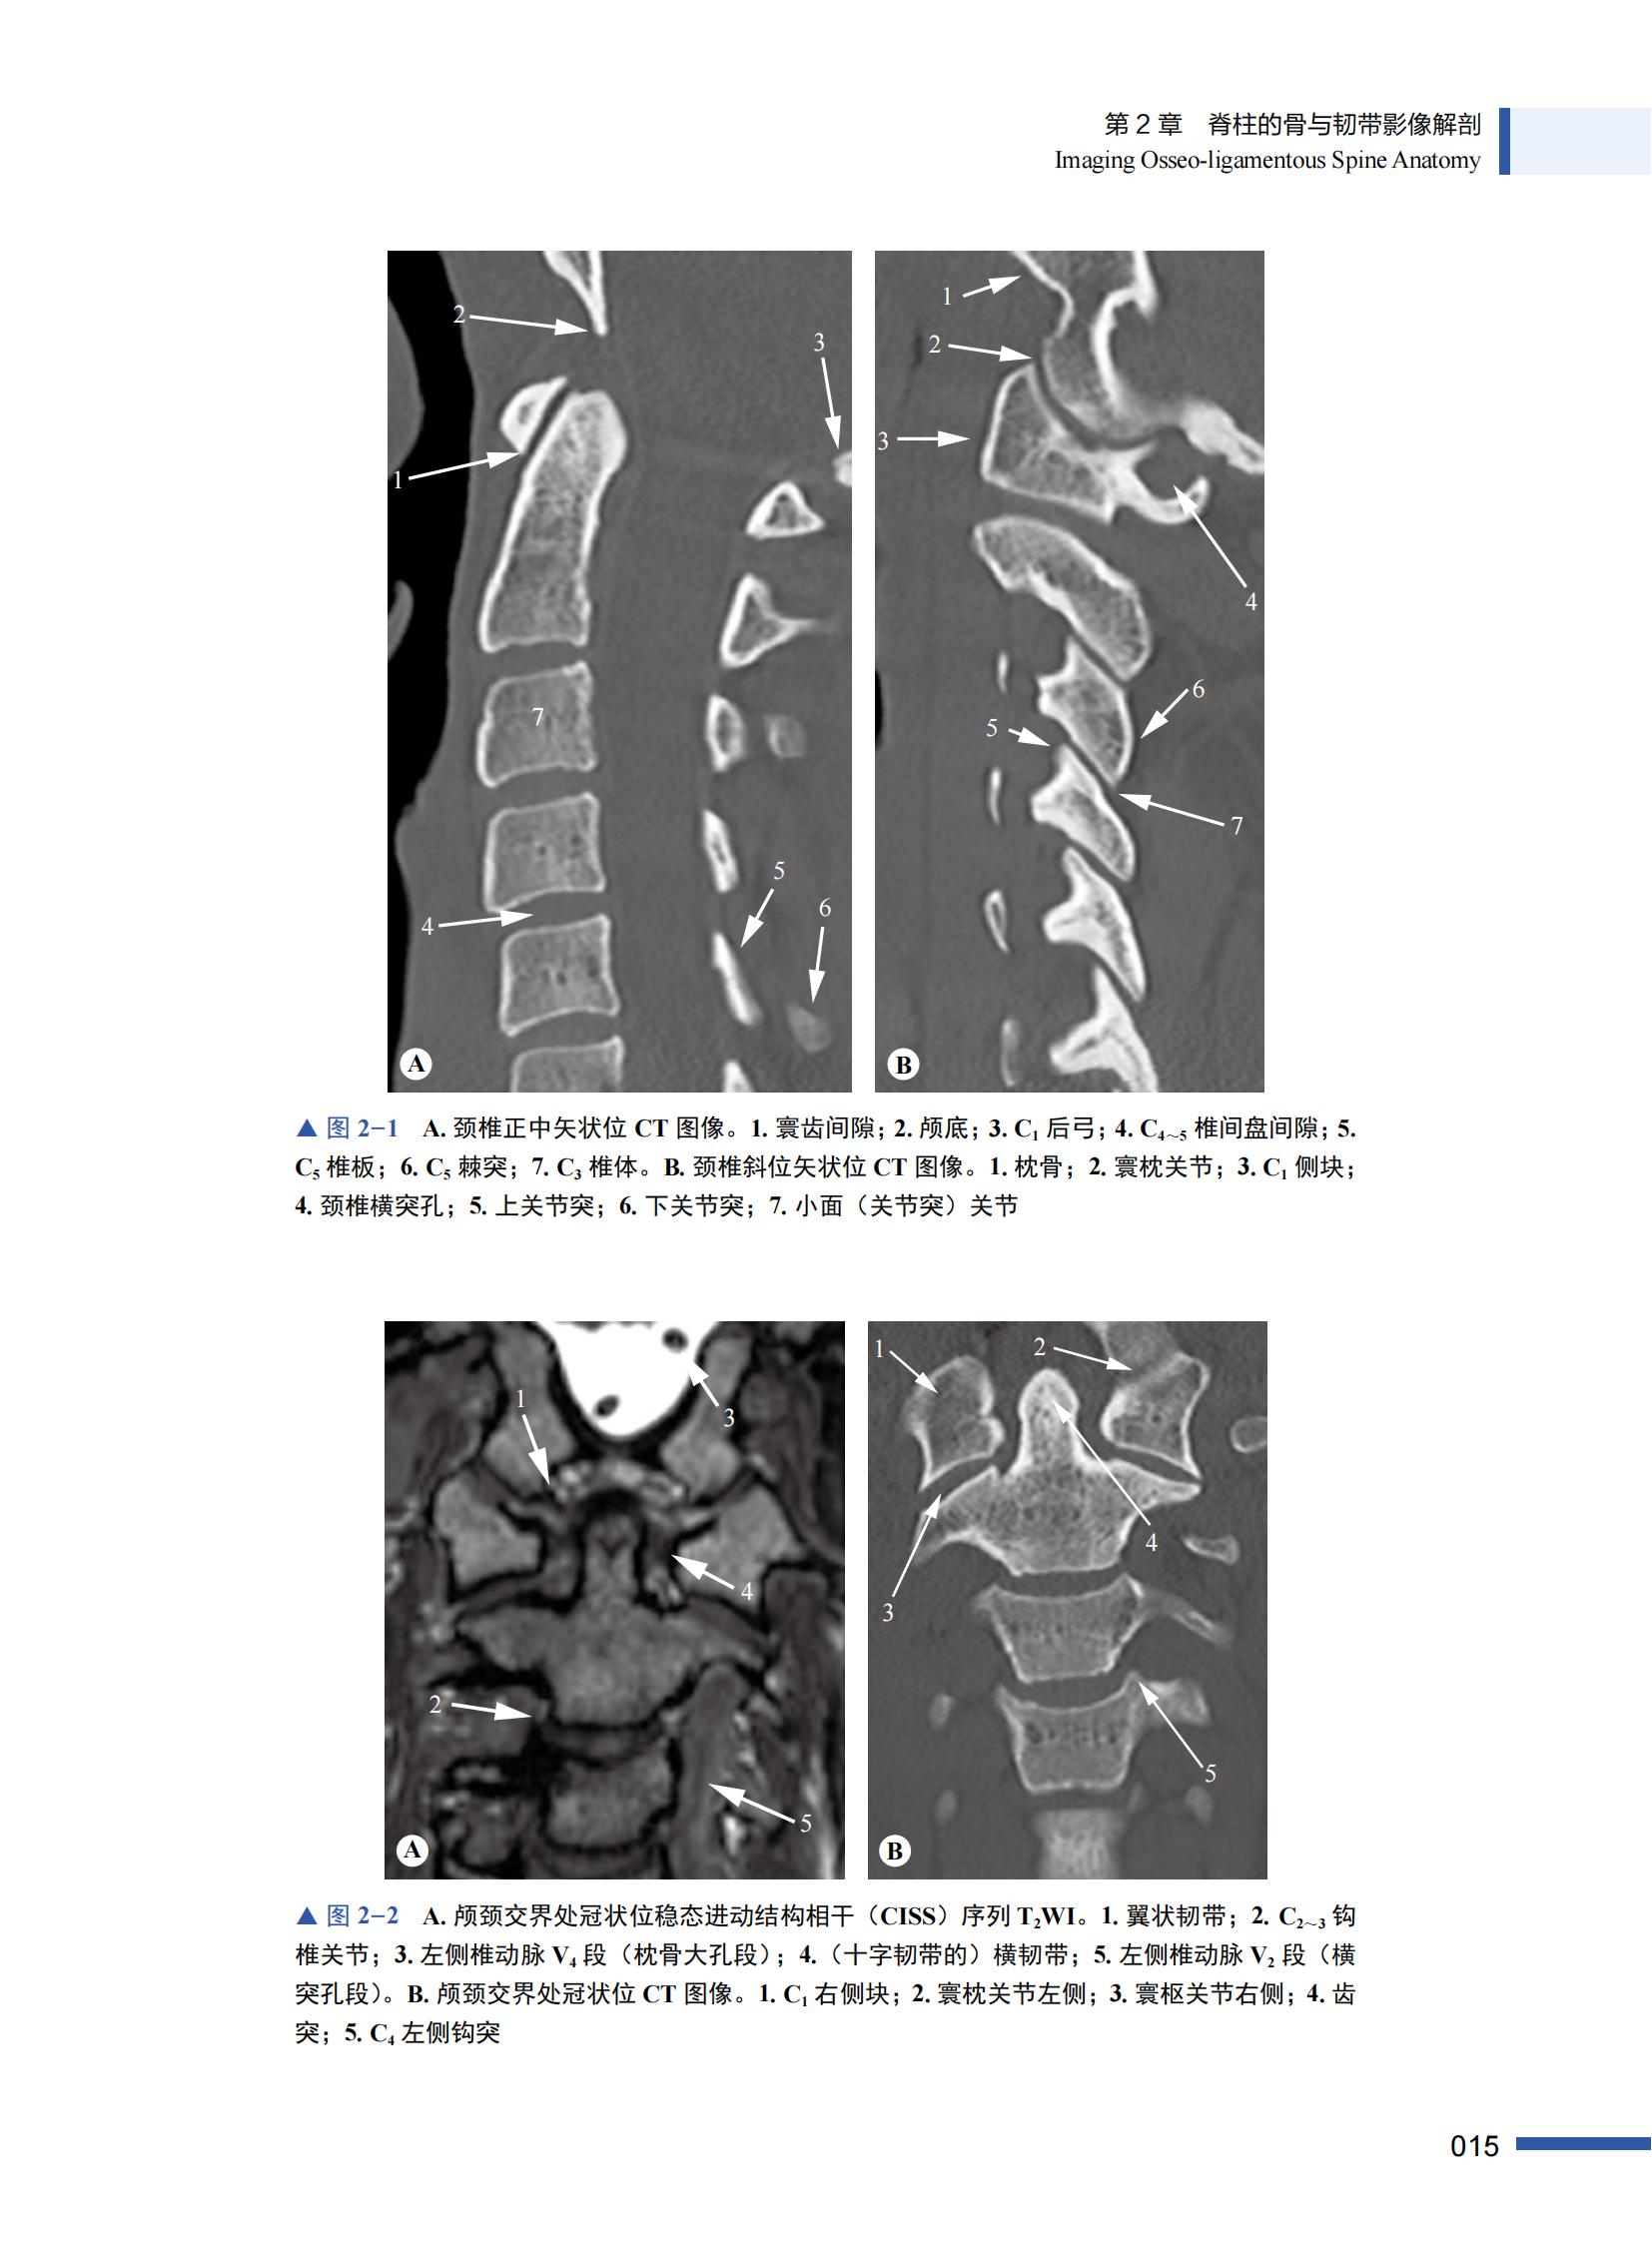

第 2 章 脊柱的骨与韧带影像解剖 014

一、临床解剖 014